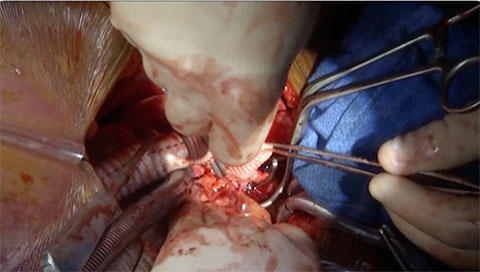

Connecting the Pump to the Apical Cuff

This video shows how to connect the pump to the apical cuff.